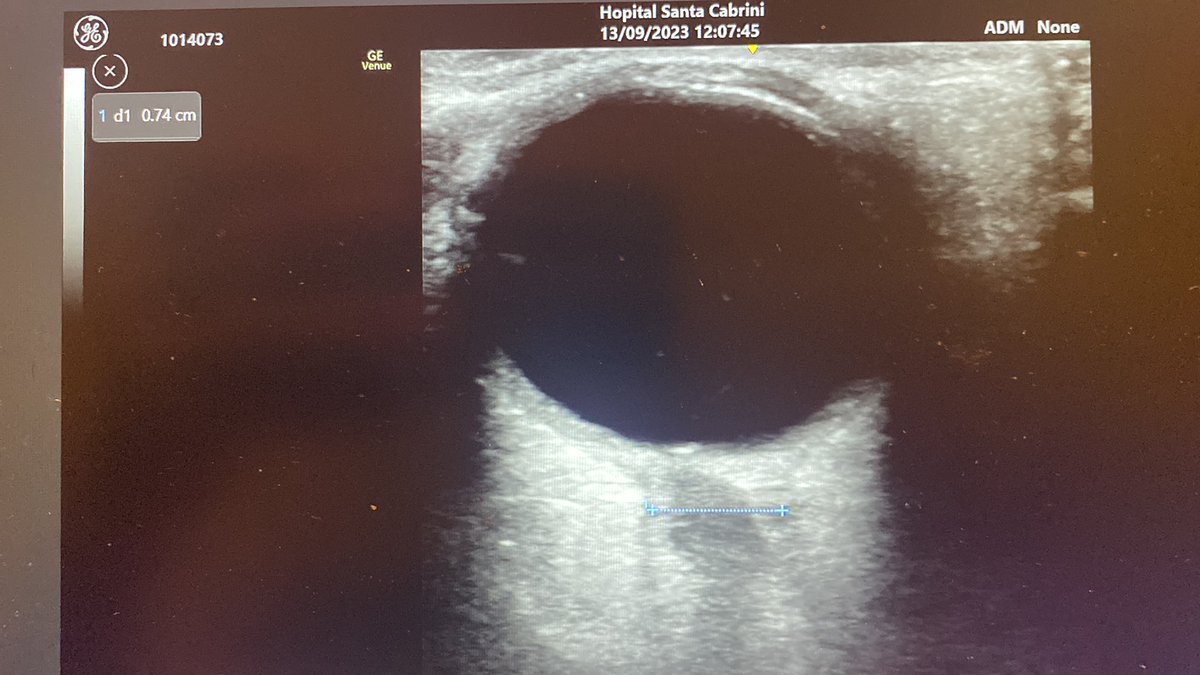

AKI in young pt with morbid obesity on mechanical ventilation and prone position (COVID-19). Cr 2.7 mg/dl. Persistent oliguria despite 2L crystalloid and Lasix gtt. BP 130/80. No vasopressor. CRT 1 sec. CPK 7000, K 6.7, UA: Blood +++, no RBC, SG 1.020, FENa 0.2% 1/